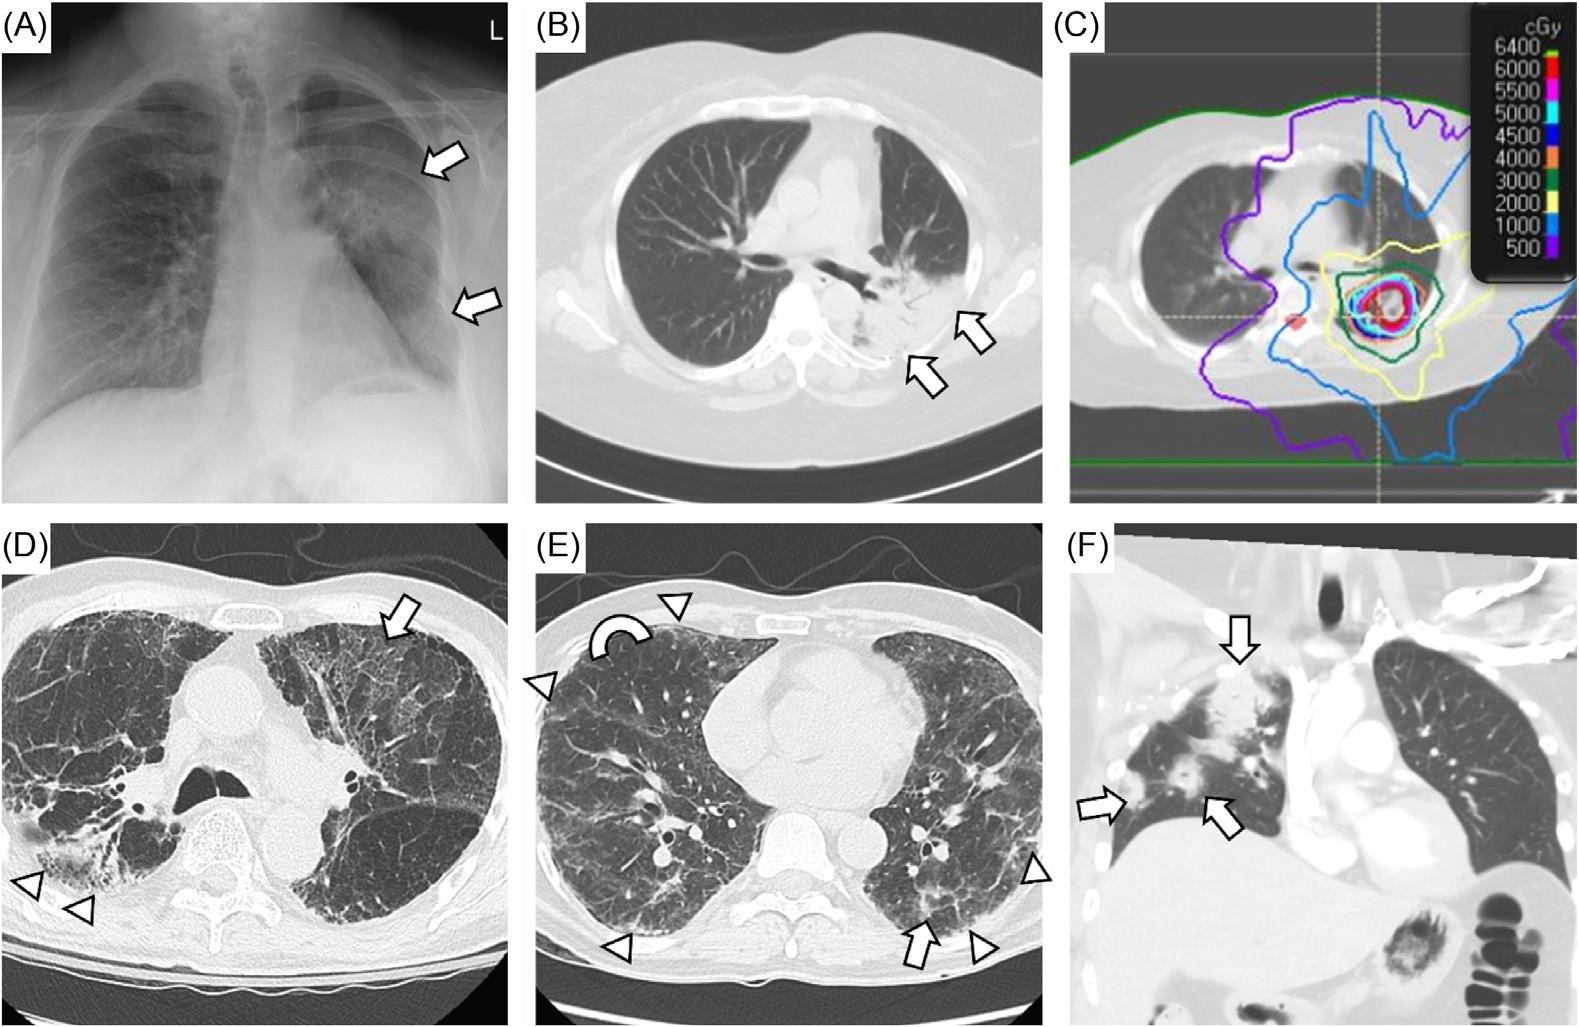

Brent King, MD, MMM University Texas, Houston

Christopher E. San Miguel, MD

Ohio State University Wexner Medical Center